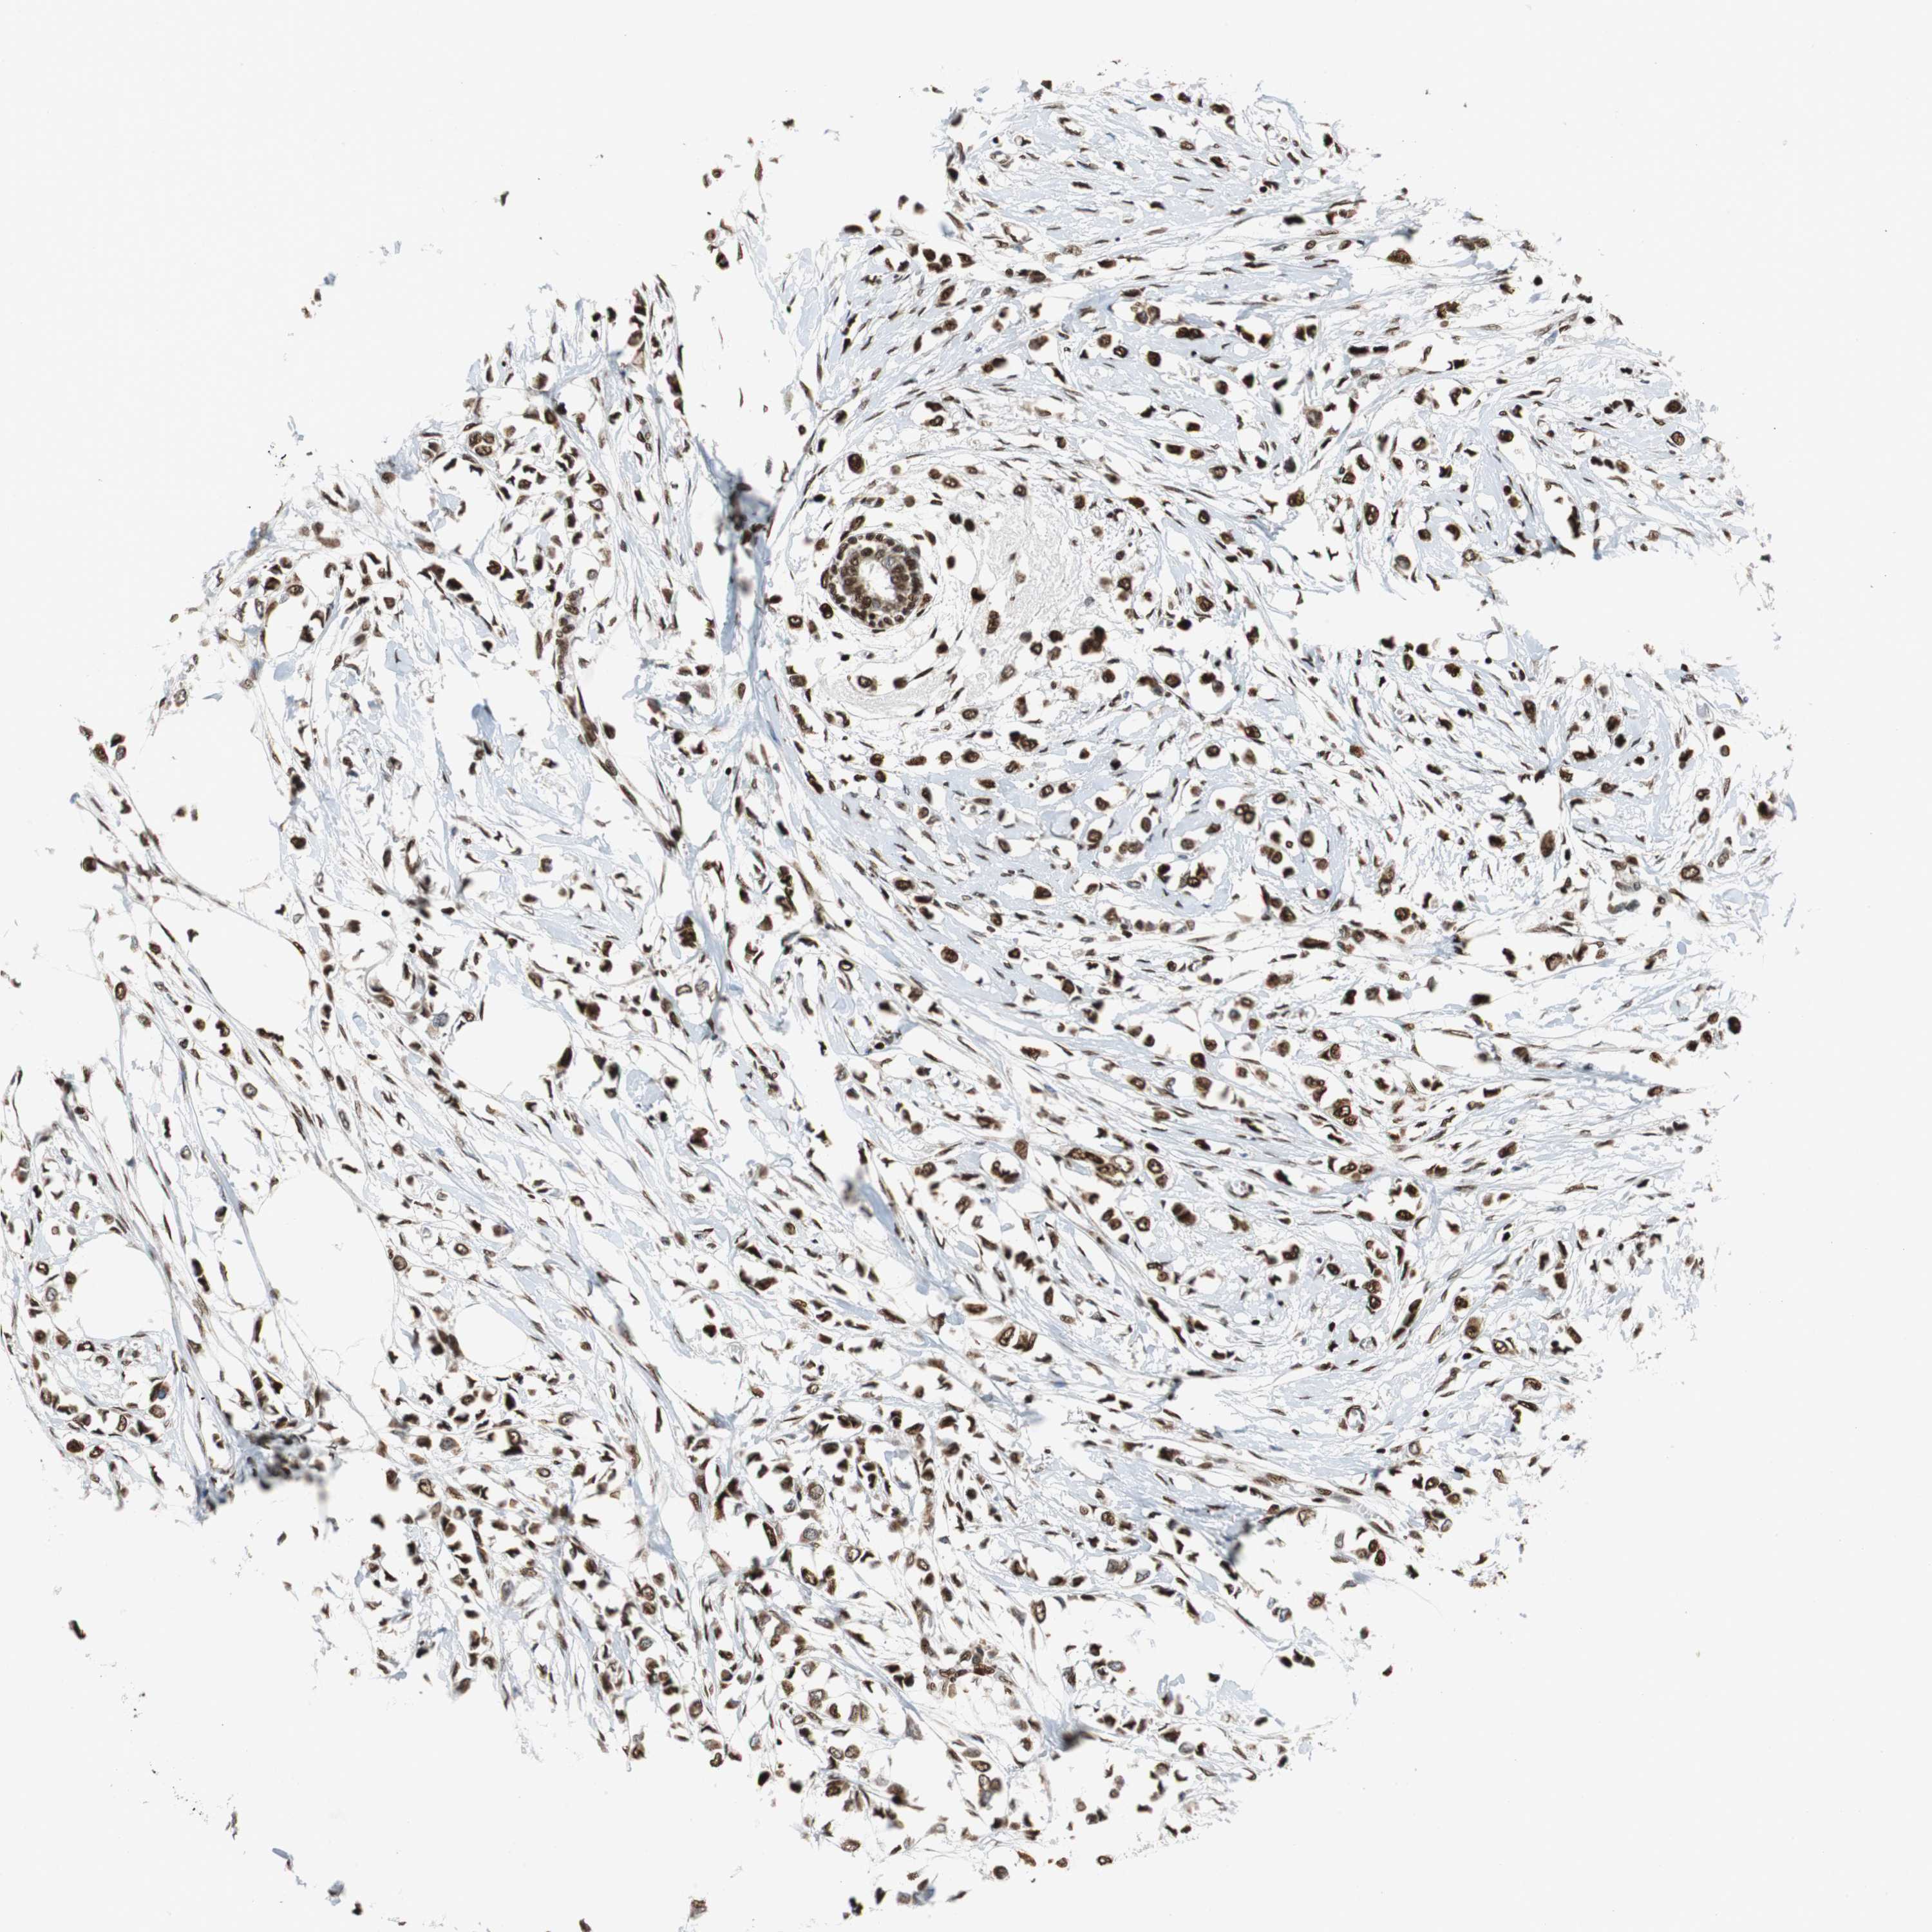

HDAC1

CANCER BREAST CANCER Show tissue menu

BRCA TCGA BRCA VALIDATION PROTEIN EXPRESSION